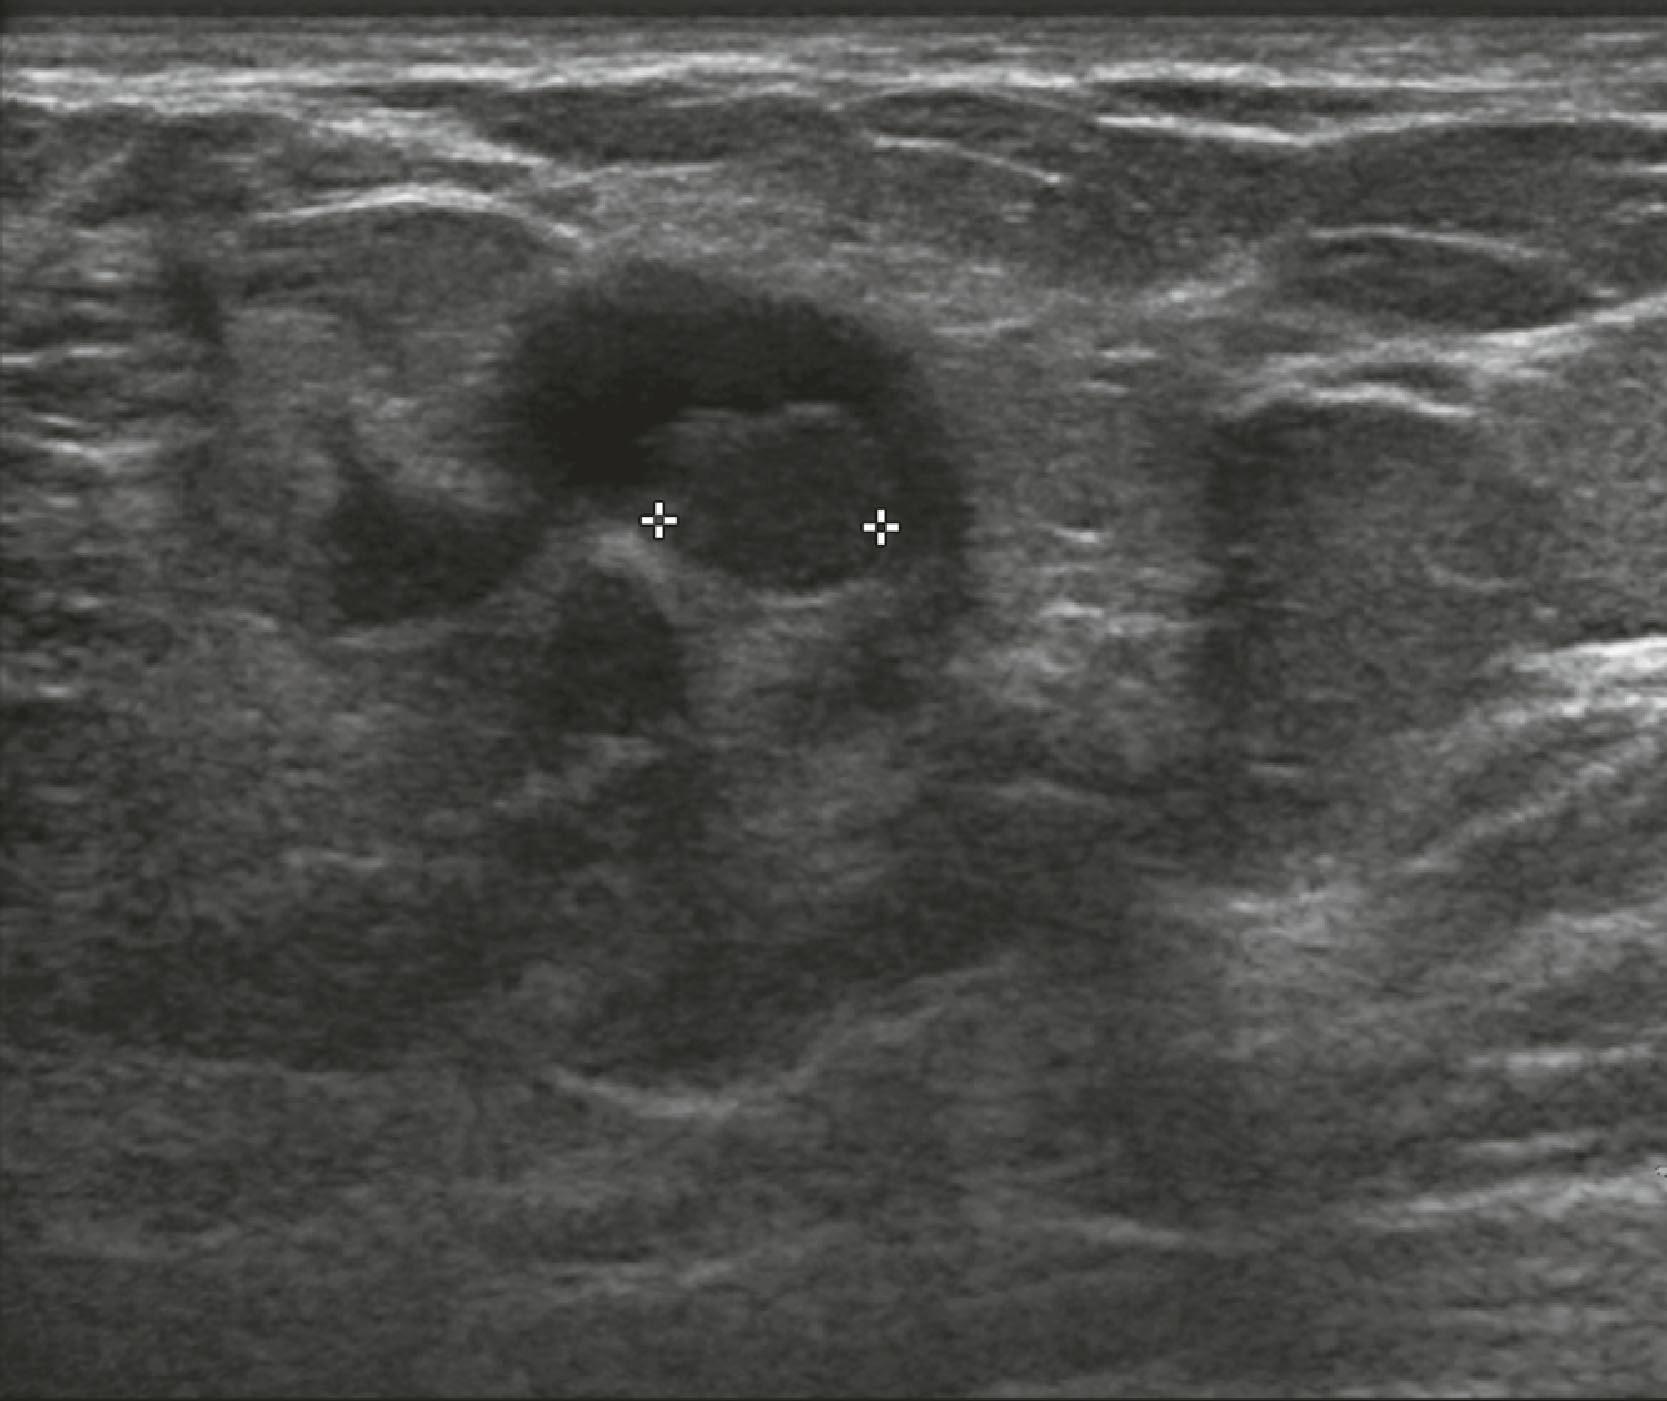

Fig. 8.13, A complicated cyst contains low-level internal echoes owing to complex fluid content, is sometimes termed a debris-filled cyst, and cannot be distinguished from a solid mass without aspiration of its contents.

Sonographic features of simple cysts include well-defined margins, anechoic contents, and acoustic enhancement (increased sound transmission through the fluid compared with the surrounding tissue) ( Fig. 8.12 ). Simple cysts are rarely aspirated except for relief of patient symptoms, and the fluid obtained is often discarded rather than sent for cytological evaluation. However, some cysts contain internal echoes and are aspirated or undergo biopsy percutaneously to determine whether they are indeed complicated cysts or solid masses ( Fig. 8.13 ). The aspirate cytology of these complicated cysts does not always contain ductal epithelial cells, leading the pathologist to report the sample as suboptimal. A complex cyst (now referred to as a complex cystic and solid mass) is one that contains a mass or has complex internal architecture and will undergo biopsy of the noncystic portion, which may represent an intracystic papilloma or carcinoma ( Fig. 8.14 ).